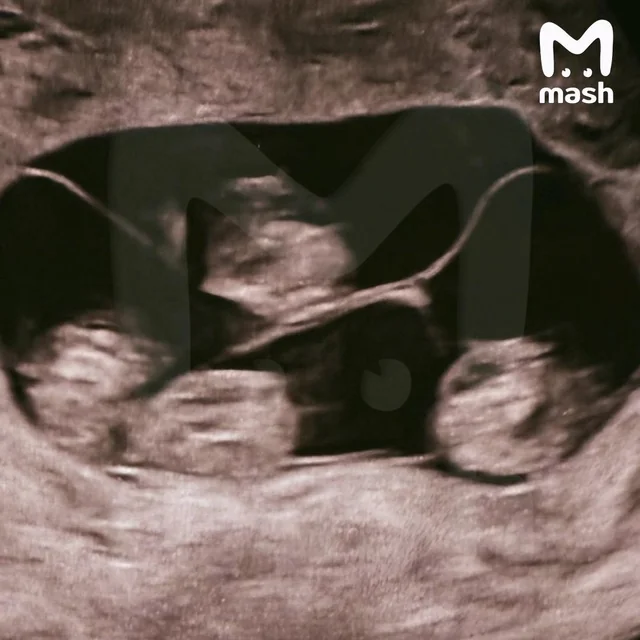

ОХУ-ын Санкт-Петербург хотын нэгэн оршин суугч тус улсын түүхэнд анх удаа нэг өндгөн эсийн дөрвөн ихэр хүүхэд төрүүлсэн талаар “Mash” телеграм суваг мэдээллээ.

Мэргэжилтнүүдийн тайлбарласнаар ийм тохиолдол 15.5 сая төрөлт тутамд ердөө ганц удаа тохиолддог маш ховор үзэгдэл юм. Шинээр мэндэлсэн дөрвөн ихэр нь хоорондоо усны дусал мэт адилхан охид ажээ. “Mash”-ийн мэдээлснээр нярай хүүхдүүдийн жин 1,360-аас 1,640 грамм, харин өндөр нь 37-оос 41 сантиметрийн хооронд байна. Одоогоор ихрүүд эмнэлгийн нарийн хяналтад байгаа юм.

Дэлхий даяар нэг өндгөн эсээс бүрэлдсэн дөрвөн ихэр ердөө 15 орчим байдаг бөгөөд тэдгээрийн 10 нь эмэгтэй ихрүүд байдаг байна.